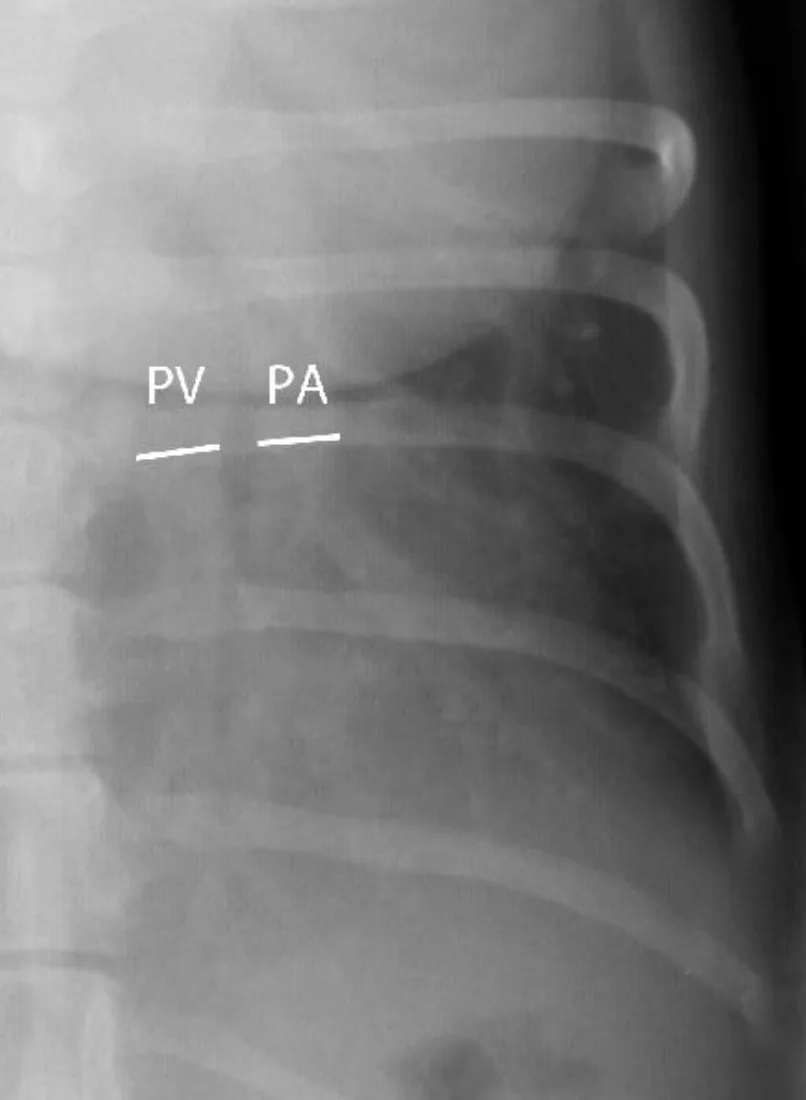

Step 2: Pleural Space

The pleural space should not be seen on thoracic images from normal animals. A very small amount of fluid, normally present between the visceral and parietal pleura, is imperceptible on thoracic radiographs; however, the pleural fissure lines or interlobar fissures may still be seen within very specific locations (Figure 3).

Right lateral (A) and ventrodorsal (B) radiographs from the same dog shown in Figure 2 with the expected locations of the interlobar fissures noted.